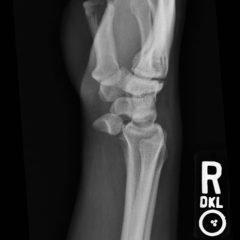

The photograph is of the anterior compartment of the right lower leg demonstrating multiple deep lacerations with exposed and torn muscle. X-ray showed no foreign body.